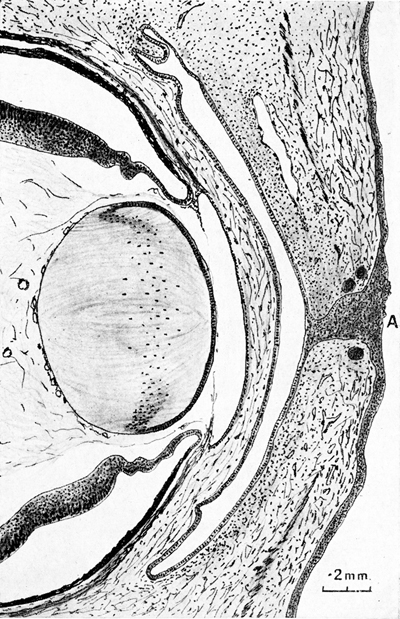

Sección de la porción anterior del ojo a los 48.0mm. de un embrión humano

A- Residuo de la Vesícula Óptica Primaria. B- Borde de la Copa Optica. C- Membrana pupilar. F- Haz de Vitreo de Druault. G- residuo de vaso capsulo-pupilar

Foto tomada de: Ida Mann ; The development of the Human Eye. 1969. Grune & Straton Inc N.Y

Dibujo de corte a través de los párpados todavía fusionados, en un embrión humano de 48 mm

A- Residuo de la Vesícula Óptica Primaria. B- Borde de la Copa Optica. C- Membrana pupilar. F- Haz de Vitreo de Druault. G- residuo de vaso capsulo-pupilar

Foto tomada de: Ida Mann ; The development of the Human Eye. 1969. Grune & Straton Inc N.Y